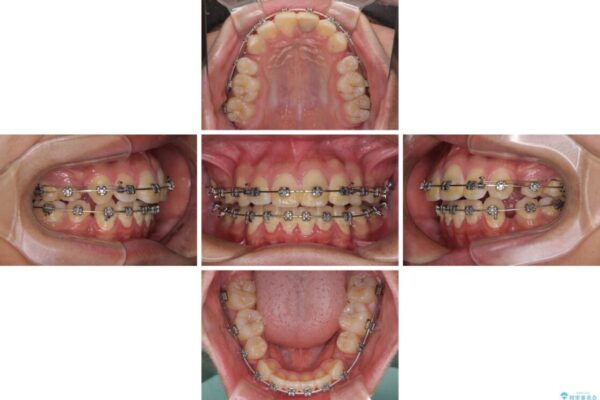

治療途中

• 膨らんだ口元 ワイヤー装置での抜歯矯正 治療途中画像

上下前歯が著しく前突している状態であったので、上下左右の第1小臼歯4本を抜歯し、ワイヤー装置にて矯正治療を行うこととしました。

舌の突出癖により、前突になったと考えられたため、舌のトレーニングをしっかりと行うよう指導しました。

小学生の頃に上顎前歯をぶつけ、歯の一部が破損している状態であったので、歯根が歯槽骨と癒着して移動しない可能性がありましたが、無事に治療を終えることができました。

受験勉強と重なり、舌のトレーニングが十分に行えず、高校生としてはやや長期間の治療となりました。